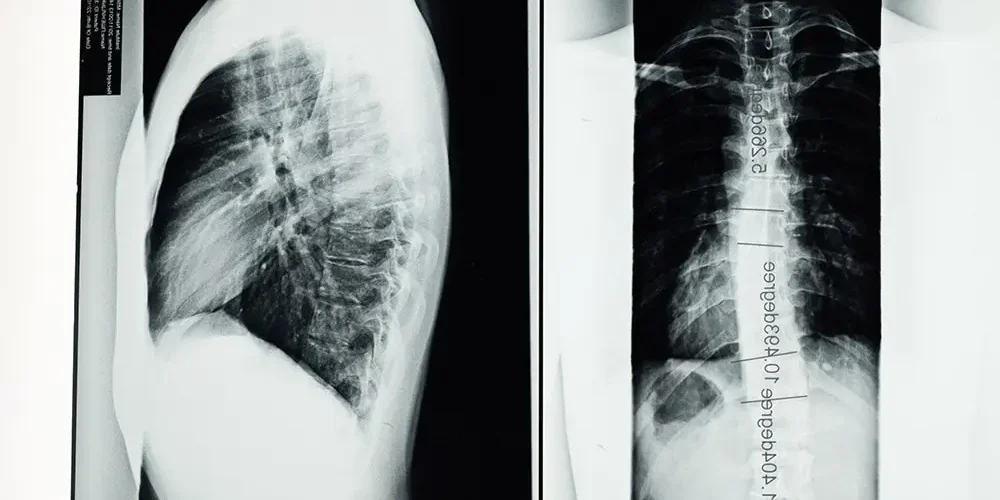

X-ray scoliosis

Scoliosis – the most important information

Scoliosis is a condition characterized by an abnormal position of the spine and its curvature. The correct shape of the spine is curved at the...